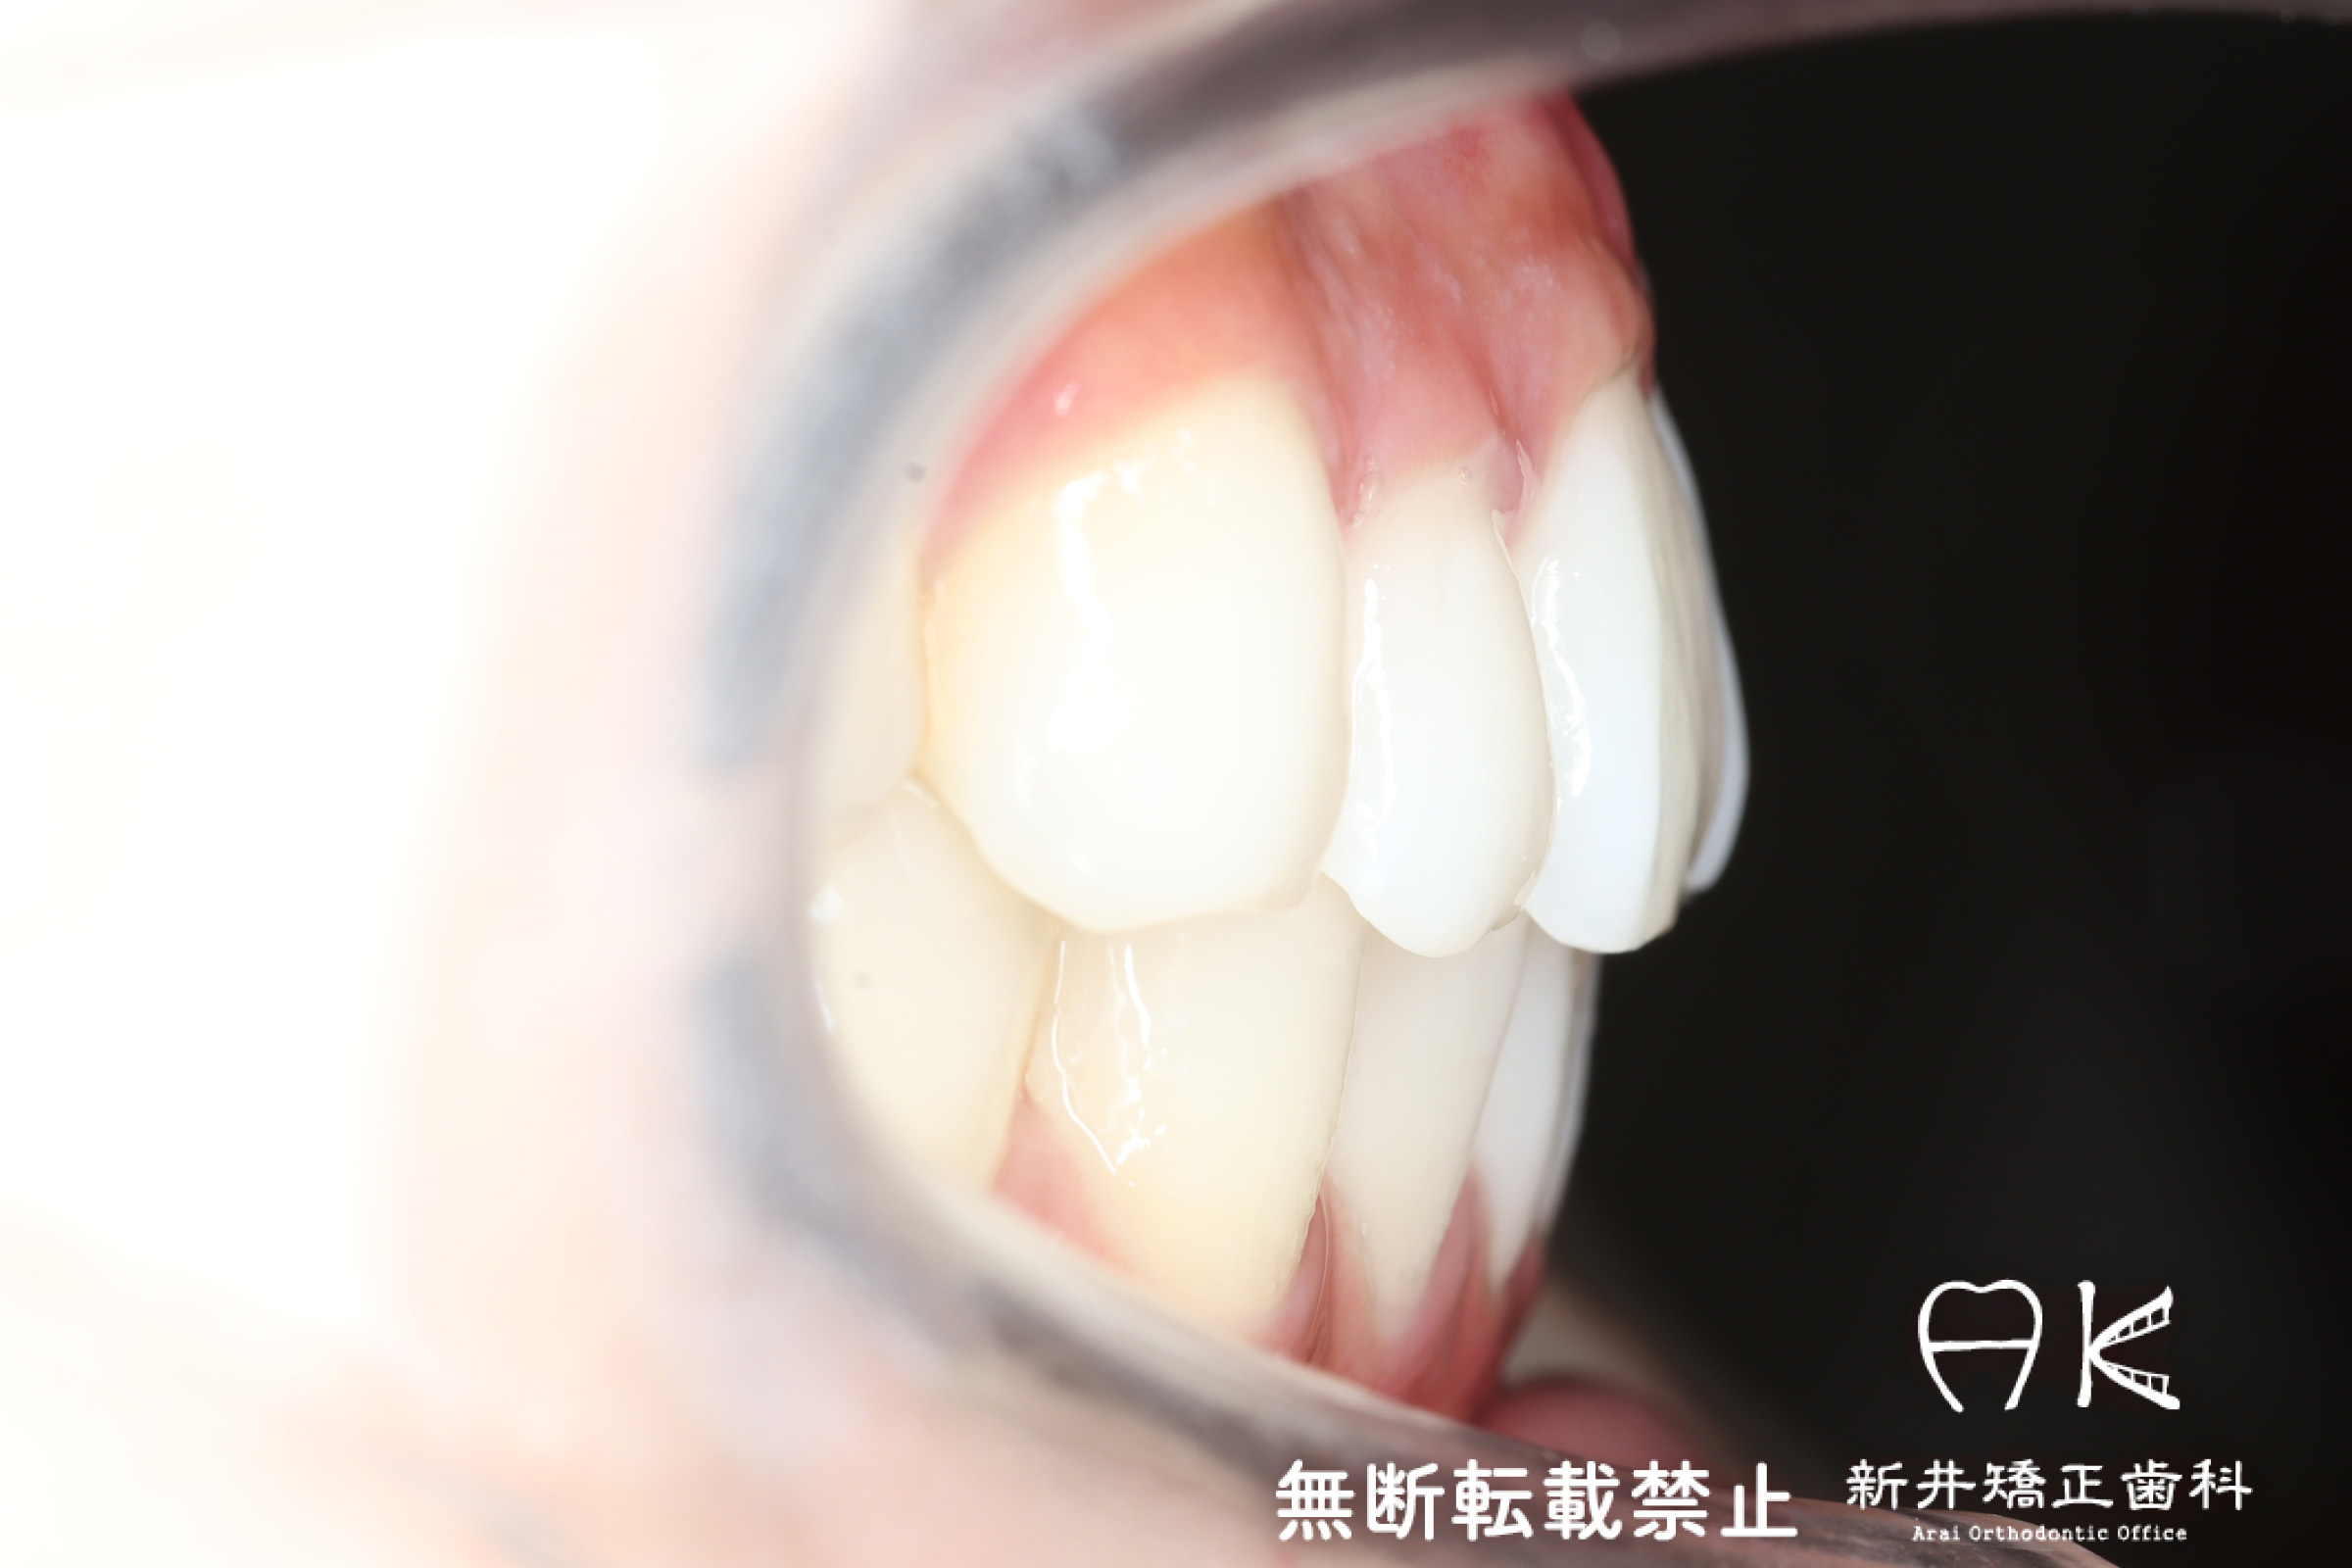

口腔内の変化

|  |  |

| ↓ | ↓ | ↓ |

|  |  |

| 治療後 | 上下の歯がお互いにはまり込み、全体的に緊密な咬み合わせになっています。 出っ歯が治り、口元の突出感が改善されて綺麗なEラインを獲得しました。 すれ違い咬合や叢生(歯のでこぼこ)も治って歯磨きがしやすく、嚙みやすい状態になっています。 |